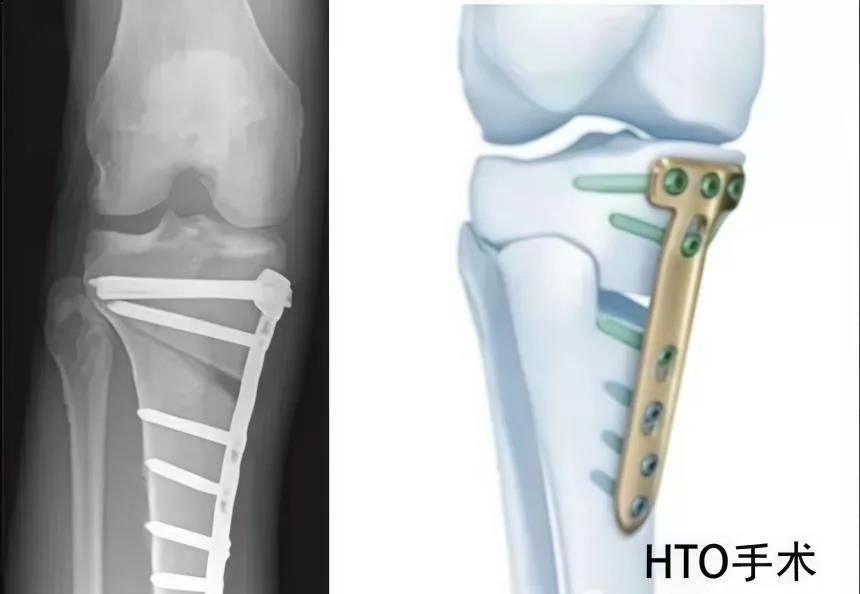

胫骨高位截骨术又是什么?

胫骨高位截骨术(HTO)是一种经典且常用的早期保膝手术。它针对膝关节内侧间室骨关节炎,通过恢复肢体力线,使膝关节内外侧间室受力重新分布,减少内侧间室受力,促进内侧关节软骨自然修复,缓解膝关节疼痛,恢复膝关节负荷及运动功能。